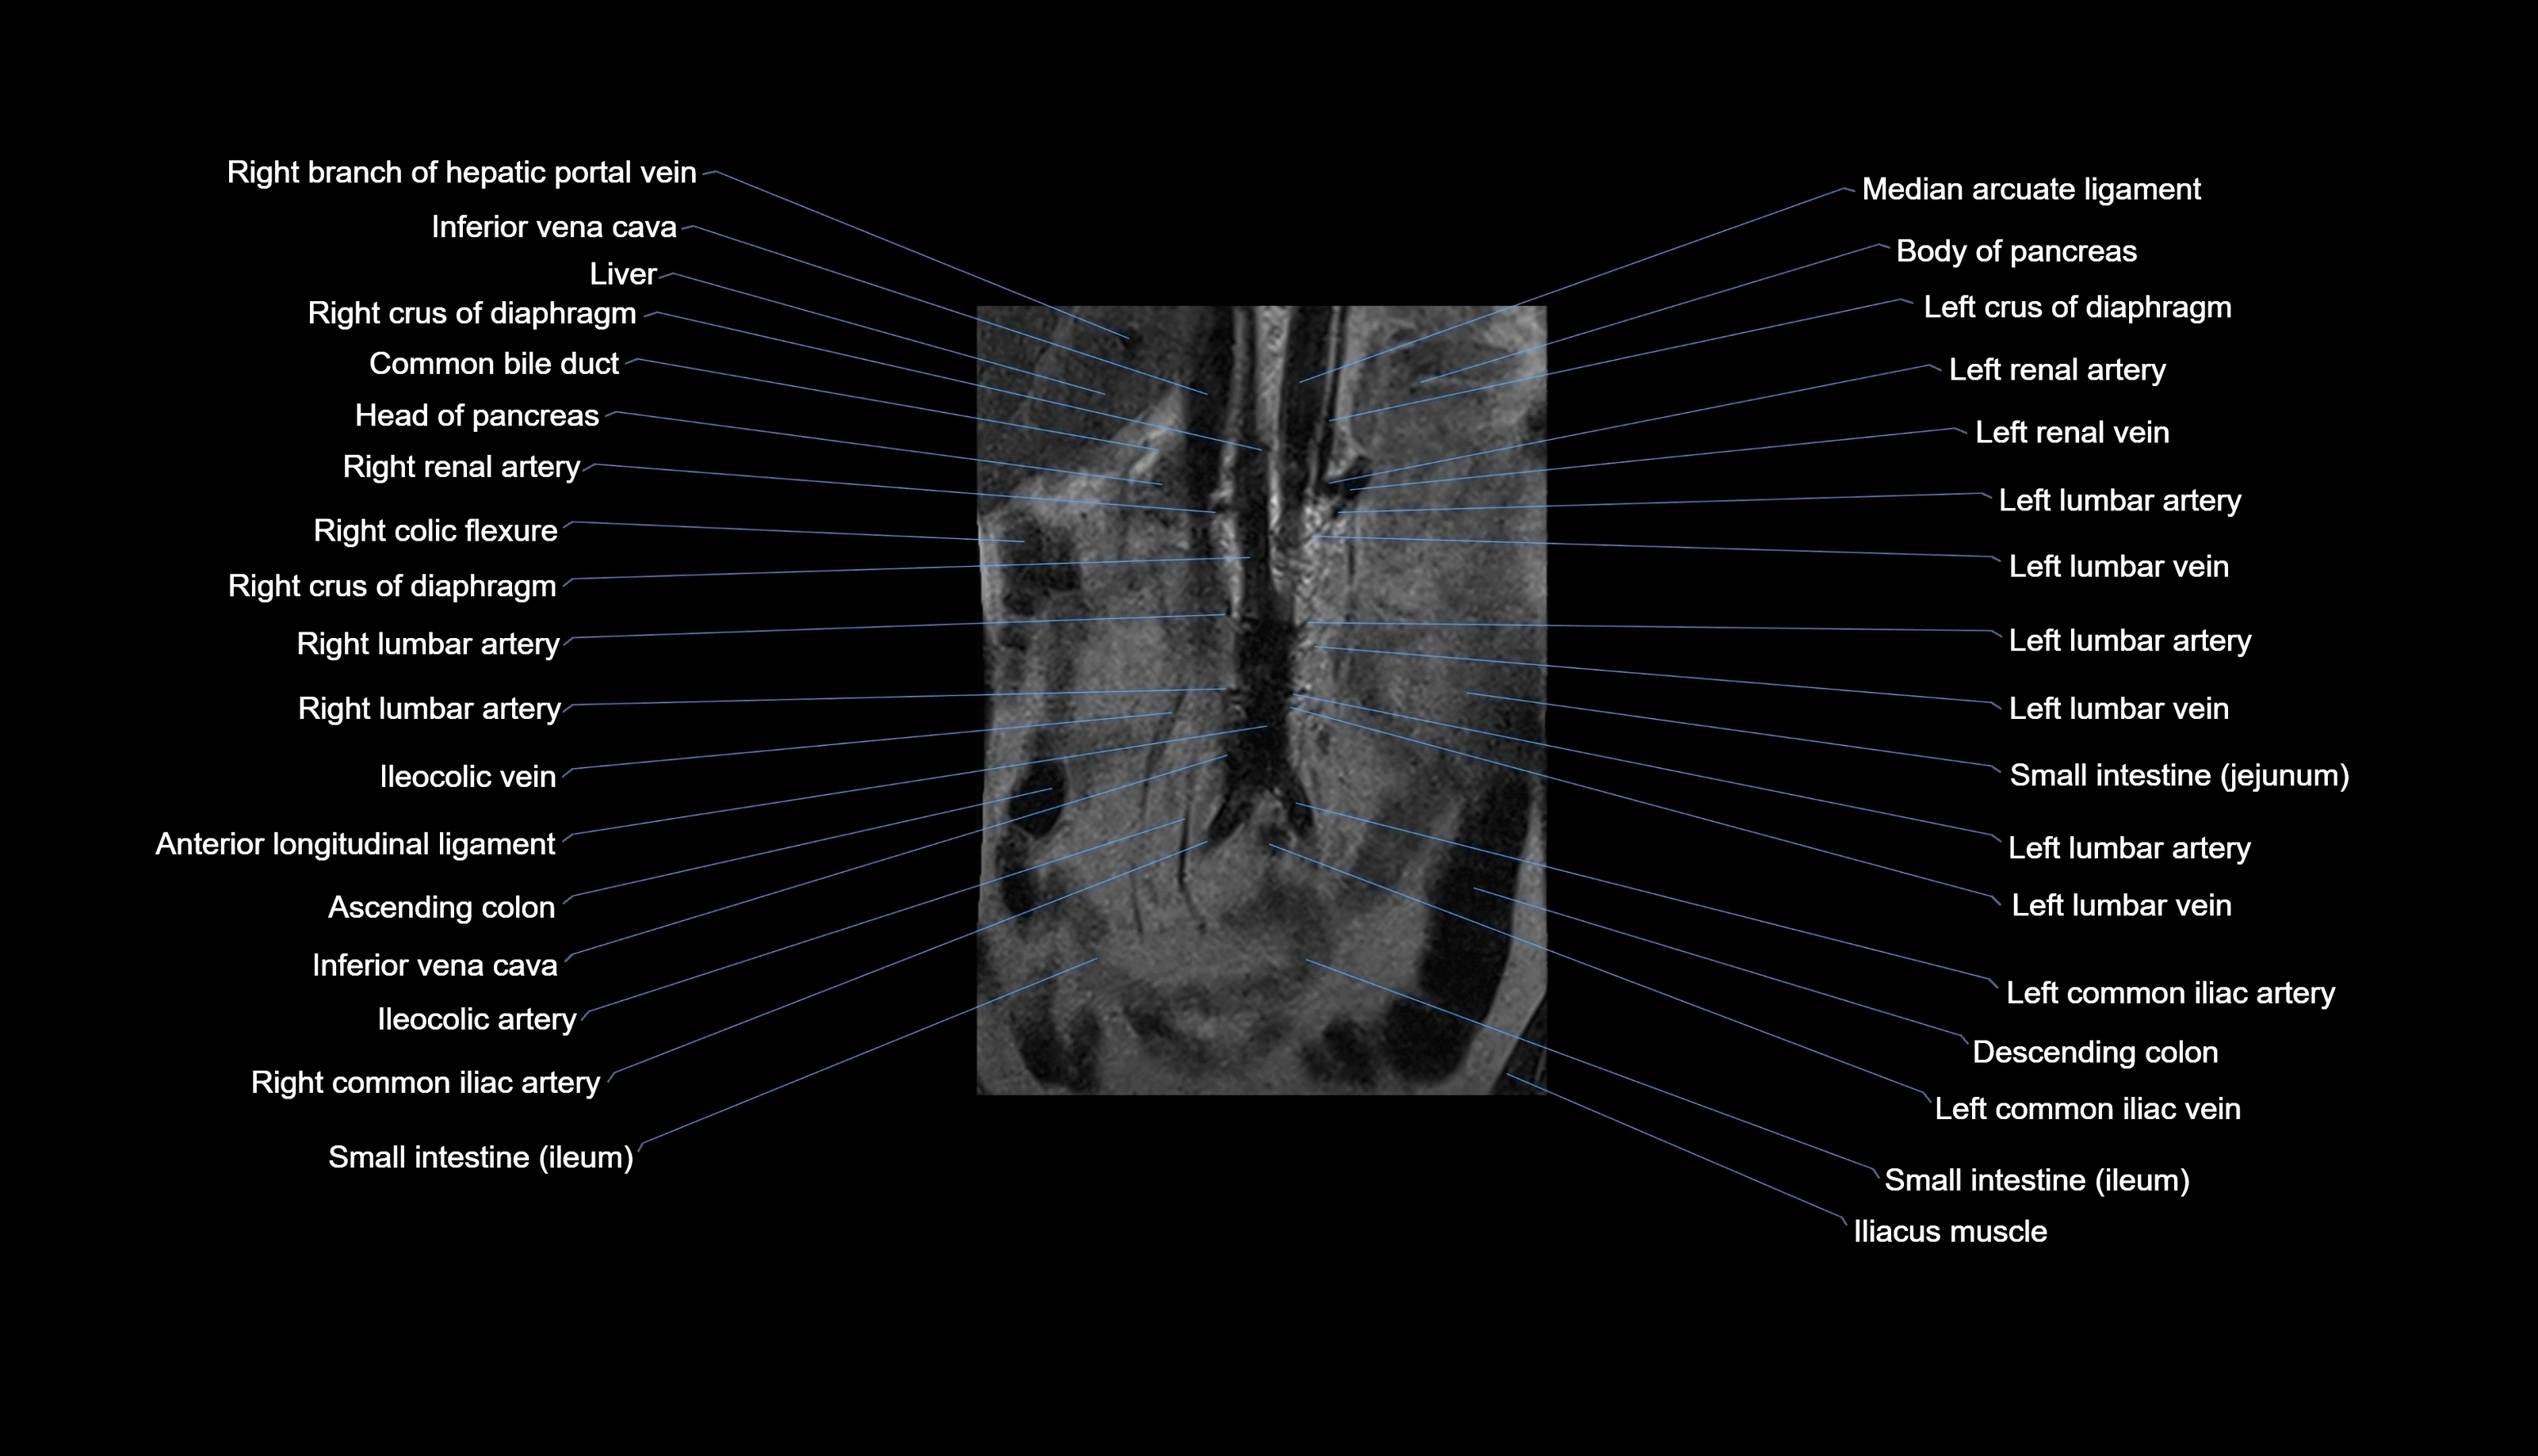

MRI images